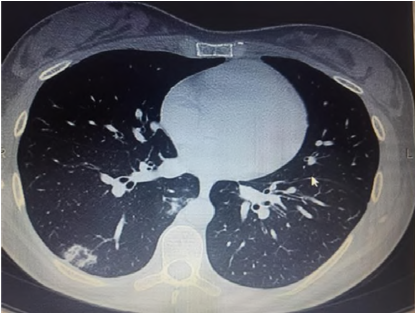

Fig. 5: Patchy GGO with crazy paving

Present study out of 107 cases 106 cases had abnormal HRCT findings out of which 99(92.5%) had bilateral abnormality and 7(6.5%) had unilateral abnormality and 7 had normal HRCT finding. Similar finding observed in [9] showed out of total of 175 chest CT scans were scored in this study. A total of 140 (80%) chest CT scans demonstrated bilateral infiltrates, and 31 (18%) chest CT scans showed unilateral infiltrates, whereas 4 (2%) chest CT scans had no abnormal findings. In our study, according to HRCT findings, GGO was seen in 70(65.4%) cases, consolidation in 34(31.8%), atelectatic band in 1(0.9%), crazy paving in 5(4.7%) cases, reticulation in 11(10.3%) cases, Peripheral hyperdensity in 9(8.4%), mediastinal LN and lymphadenopathy 2(1.9%) cases respectively, 1(0.9%) case with COPD, ground glass haziness, emphysematous changes, mild Fibrosis and septal thickening respectively. Similar findings observed in Sudhir Bhandari et al.119. (2020) showed that in an early phase of disease (10 d), among radiologically positive patients (8 out of 15) 12.50% patients had GGO, 75.00% patients had both GGO and consolidation, while remaining 12.50% patients had only consolidation in imaging of HRCT chest.